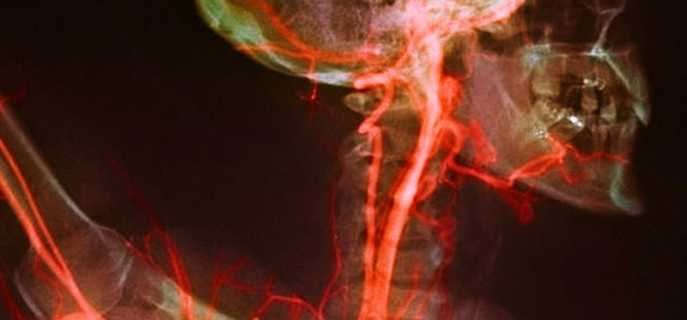

- Церебральная ангиография или рентген с контрастом предполагает введение вещества с помощью катетера под контролем флюороскопа и последующее выполнение рентгеновских снимков.